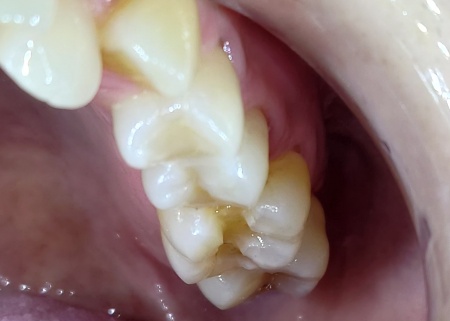

治療後

虫歯治療後に行う修復方法について、以下の提案を行いました。 ①保険診療で修復 ②自費診療で修復 患者様はそれぞれメリットとデメリットをしっかりご理解いただいたうえで、②の自費診療での治療を選択されました。 まず、取り残しがないようにしっかりと虫歯を除去し、歯の形を整えてから型取りを行いました。 後日、完成したE-MAXインレーを装着し、噛み合わせや見た目に問題がないことを確認して、治療を終了しました。 |